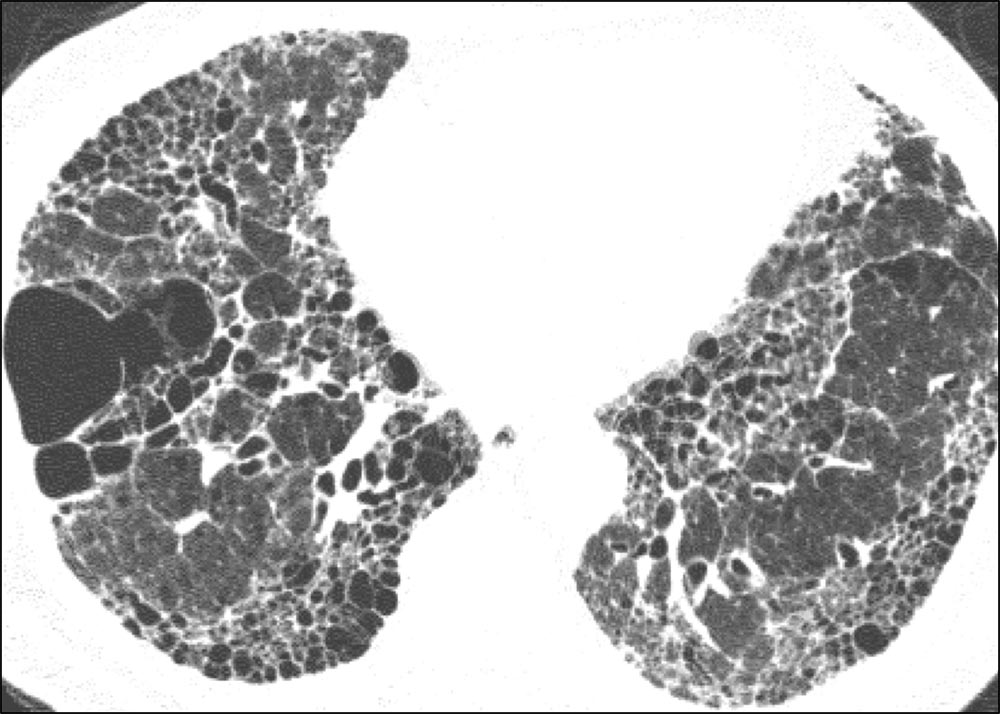

Axial HRCT image showing basal- and peripheral-predominant reticulation and honeycombing. These features are consistent with usual interstitial pneumonia.

Image courtesy of and used with permission from Sudhakar Pipavath, MD.